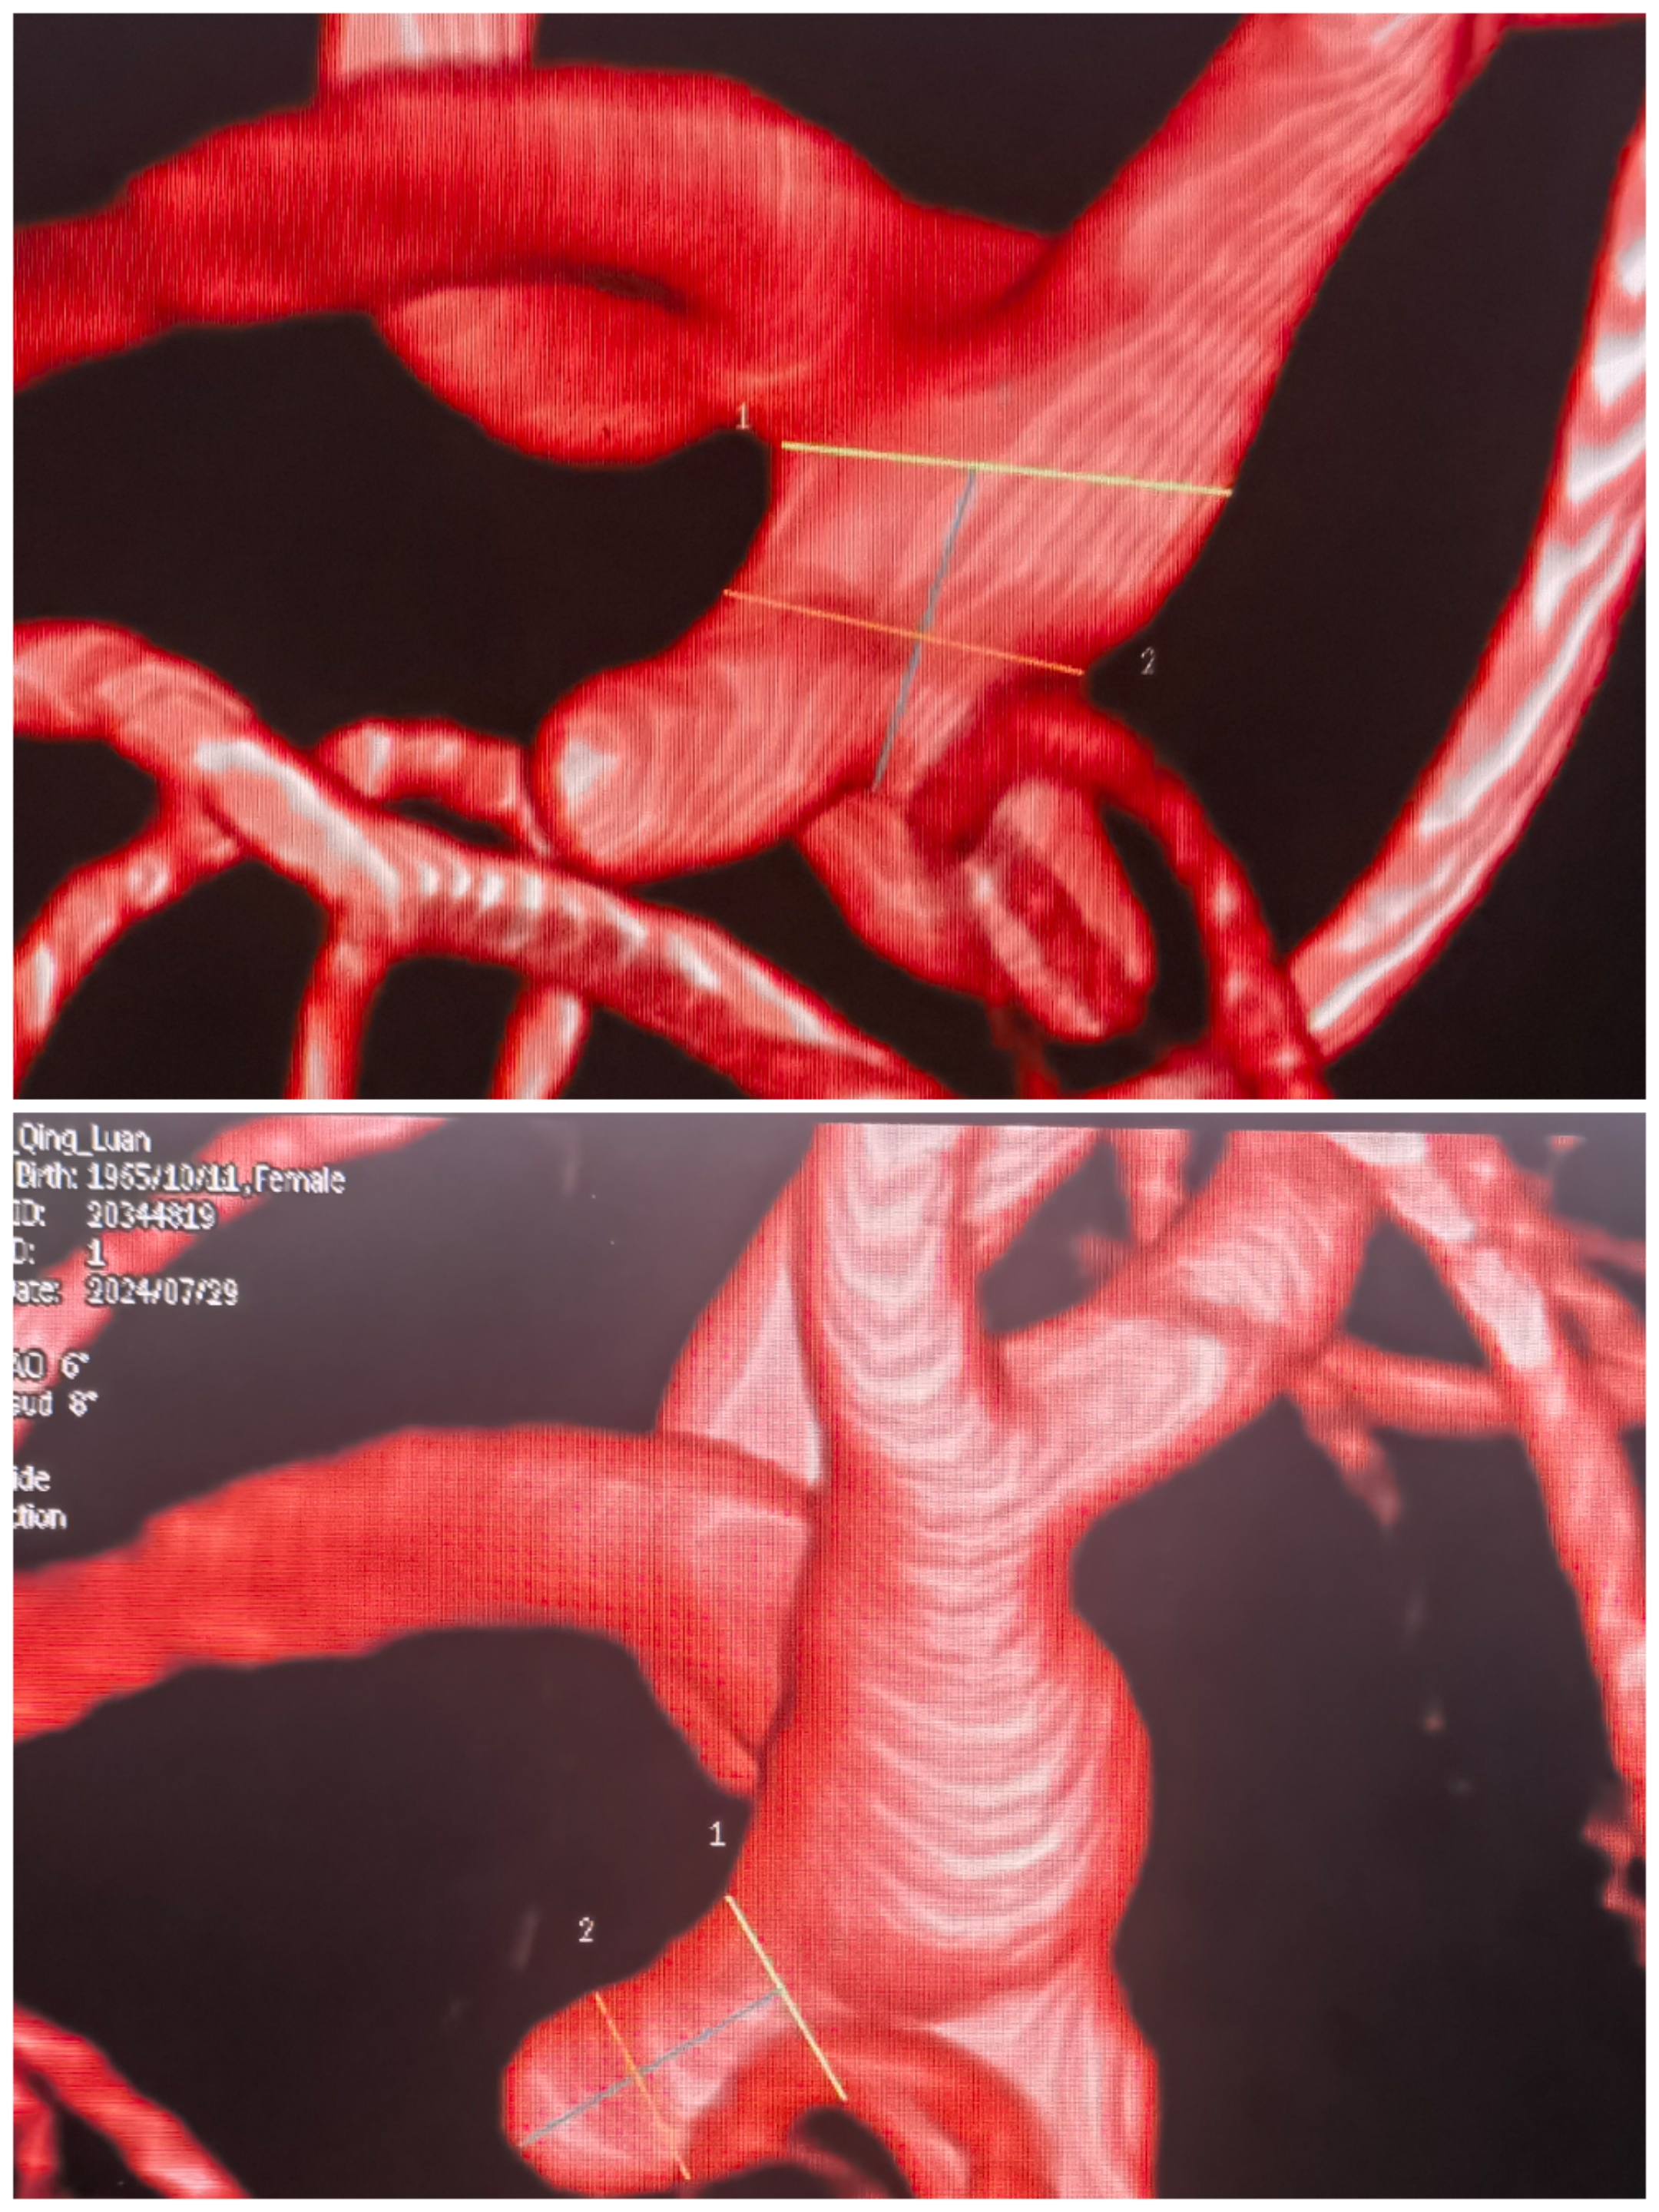

CTA提示不规则分叉部、多分叶、动脉瘤,瘤颈波及上干为主

3D重建情况